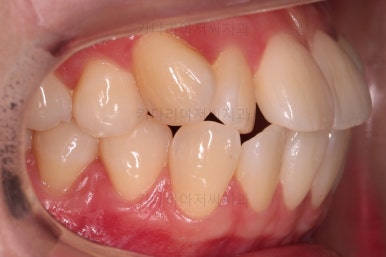

마찬가지로 초진 시 입안의 모습인데요.

전반적으로 약간 삐뚤지만 특히 윗니 앞니가 삐뚤고요.

송곳니는 덧니처럼 튀어나와 보이네요.

그리고 전반적으로 치아가 앞쪽으로 경사되어 있어서 앞니는 뻗친 느낌이 있네요.

가지런하게 하면서 앞니를 뒤로 당겨줘야 여러 가지 문제점들이 개선되기 때문에 발치교정을 했어요.